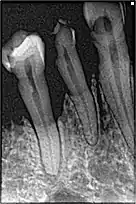

La perte osseuse chez un fumeur

- tabac : facteur de risque majeur. Le tabac, en entraînant une mauvaise vascularisation de la gencive, va énormément influencer l'apparition des premières lésions en diminuant les défenses immunitaires. La consommation du tabac intervient sur la prévalence et la sévérité des parodontites de l'adulte, ainsi que sur les parodontites réfractaires et la gingivite ulcéronécrotique[6],[18],

La parodontite s'accompagne d'une perte osseuse, appelée alvéolyse (ce qui signifie « destruction de l'os alvéolaire »).